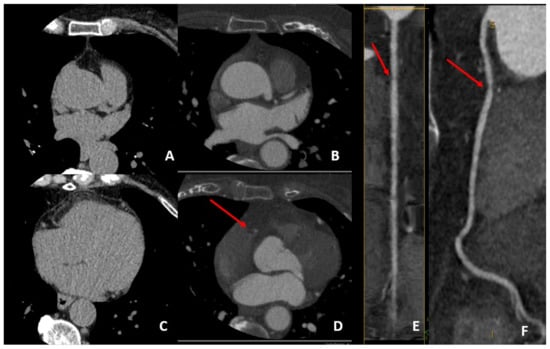

| High-Risk Feature | Definition | Example |

|---|---|---|

| Remodeling index (RI) | Ratio between lesion plaque area (red circle) and reference lumen area (blue circle). Positive remodeling is defined as RI > 1.1. | ![]() |

| Low-attenuation plaque (LAP) | Presence of any voxel < 30 HU in a coronary plaque. | ![]() |

| Plaque burden (PB) | Derived by the following formula: (lesion plaque area (red circle)—lesion lumen area (blue circle))/lesion plaque area (red circle). | ![]() |

| Napkin-ring sign (NRS) | Presence of rim-like thin enhancement (no more than 130 HU) distributed along the outer contour of the vessel and surrounding a fibro-lipidic plaque. | ![]() |

| Small spotty calcifications (SC) | Any discrete calcification ≤ 3 mm in length and occupying ≤ 90° arc when viewed on short axis. | ![]() |